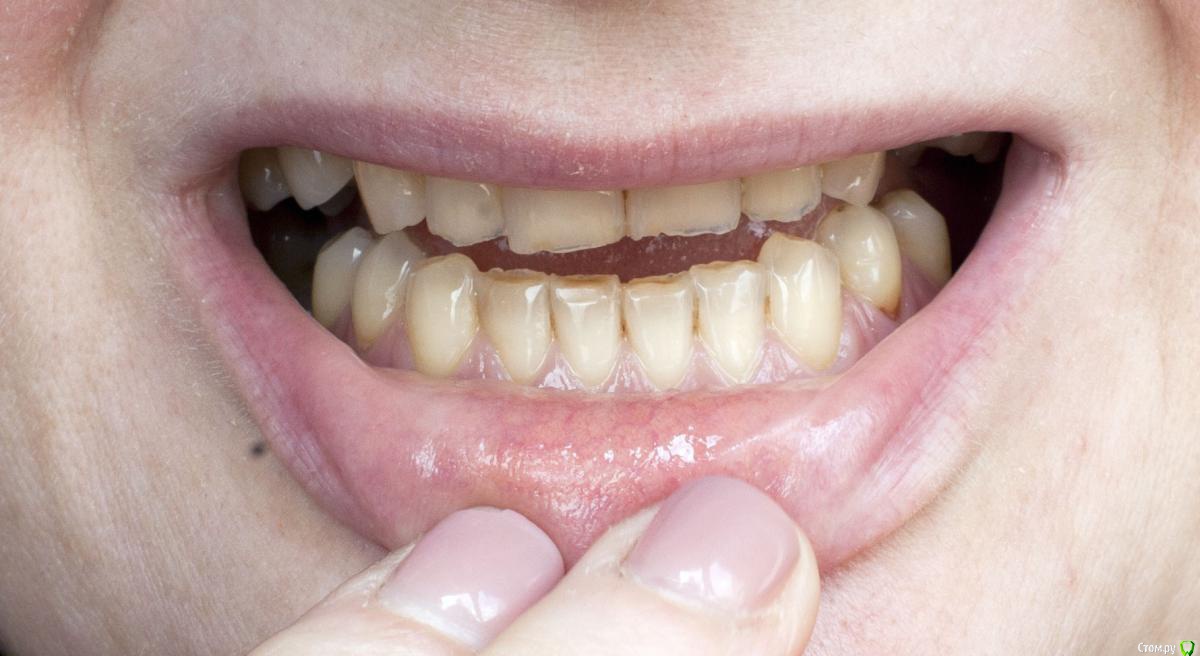

Barbar Опубликовано 21 июля, 2015 Автор Поделиться Опубликовано 21 июля, 2015 что именно Вам мешает широко улыбаться??? форма зубов, их расположение, отсутствие боковых зубов...? что именно Вы хотели справить с помощью брекетов? Вам стоматолог посоветовал заниматься прикусом или это Ваши предположения? если хотите просто поставить отсутствующие зубы - то Вам к ортопеду надо. Он посмотрит и скажет , ДОСТАТОЧНО ли места по ширине и высоте для имплантации и протезирования. если да, то просто протезируйтесь. Если же нет - то тогда Вам к ОРТОДОНТУ. Да, да и да! " форма зубов, их расположение, отсутствие боковых зубов..."Ладно, их расположение устраивает, во рту они как раз на правильном месте %РМне не нравится, что зубы пожелтели, неровны и сточены, особенно нижние. И прикус!Верхние зубы направлены немного вовнутрь и перекрывают нижние, у которых от этого сильный наклон вовнутрь. Уж не знаю как лучше объяснить, я не врач и терминами не владею. Думала, что всё понятно по фото. Улыбка получается жалкая. Имплантаты на место отсутствующих зубов будут ставить, уже решено. 6 штук, что недёшево. Но хотелось наконец решить эту проблему так, чтобы не было мучительно... то есть все продумать и закрыть тему зубов на долгие годы. Исправить прикус тоже.Мои вопросы были - с чего начать? Какие варианты? Помогут ли (для прикуса) просто коронки на передние нижние зубы? тогда придётся закрыть коронками весь ряд? или только 6 зубов? Или поставить имплантаты и постепенно исправлять прикус лигвальными брикетами? Но тогда высота имплантатов после исправления будет недостаточной? Ссылка на комментарий

Barbar Опубликовано 23 июля, 2015 Автор Поделиться Опубликовано 23 июля, 2015 И причём безо всяких брикетов. По сценарию: пришла, заснула, очнулась - мне зубы, а ему деньги. Я думаю, это мечта любого стоматолога (прошу не обижаться, это добрая шутка)По поводу эстетики - вам правда мои зубы кажутся в полном порядке или просто у вас мои фото в полный размер не открываются? На последней фотографии особенно видно, что нижние зубы сточены и пожелтели, а верхние неровные, имеют зазубренные края и частично уже прозрачные, или нет? Вы, как стоматолог, можете видеть проблемы в зубах, кажущихся идеальными, что простым смертным не под силу, и при этом мои зубы Вам кажутся вполне эстетичными? Ссылка на комментарий

Yana guapa Опубликовано 23 июля, 2015 Поделиться Опубликовано 23 июля, 2015 Нет, он предложил именно коронки. коронки в наше время и при Ваших неразрушенных зубах? нет! показаний к коронкам у Вас нет. если и делать - то тонкие накладки на зубы - виниры. Они крепятся только спереди и "спиливается" ооочень мало эмали, буквально для сцепления. чтобы поставить коронки - нужно спилить эмаль вокруг всего зуба. Плюс у Вас очень плотный контакт между верхними и нижними резцами (чтобы рот закрывался как раньше - надо будет много спилить, чтобы коронки "вместились " в это пространство ) (коряво, на пальцах объясняю) Ссылка на комментарий

Yana guapa Опубликовано 23 июля, 2015 Поделиться Опубликовано 23 июля, 2015 По поводу эстетики - вам правда мои зубы кажутся в полном порядке или просто у вас мои фото в полный размер не открываются? На последней фотографии особенно видно, что нижние зубы сточены и пожелтели, а верхние неровные, имеют зазубренные края и частично уже прозрачные, или нет? Вы, как стоматолог, можете видеть проблемы в зубах, кажущихся идеальными, что простым смертным не под силу, и при этом мои зубы Вам кажутся вполне эстетичными?многие пациенты позавидовали бы Вашим зубам )) пусть и боковые Вы по каким то причинам потеряли , но передние зубы здоровые.немного стерлись режущие края (но вы не забывайте что и со временем у всех людей стираются зубы, ну и конечно Вы их повышенно истирали в связи с отсутствием боковых зубов). их можно заполировать просто. Я так понимаю что все-таки Вас больше беспокоит непосредственно расположение зубов, степень их обнажения при улыбке - это тогда исправлять только брекетами. Вообще - улыбку нужно уметь носить и преподносить!)) Возможно можно ее дополнительно оформить, например, сделать губы немного пухлее, тогда вся улыбка станет выразительнее. как вариант - подумайте) Ссылка на комментарий